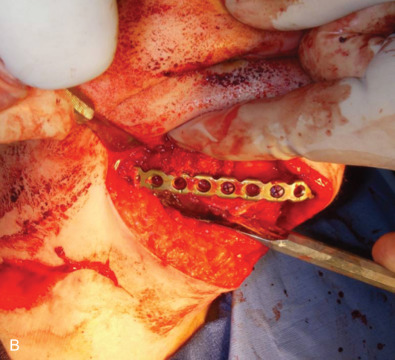

All of these systems allowed for convalescent function – life without MMF. RIF had the potential of dramatically shortening the course of treatment. However, its use was highly technique-sensitive with a steep learning curve. Thus, the incidence of complications increased dramatically due to operator error. Complications related to inadequate reduction – “the OIF” (open internal fixation … without the reduction) ( Figs. 1.16.1–1.16.3 ), inadequate fixation ( Figs. 1.16.4–1.16.7 ) and surgical misadventure ( Fig. 1.16.8 ) began to appear. Indeed, by the early 1990s operator error was the number one cause of mandibular fracture complications. Quite obviously, RIF is very unforgiving. When done poorly, one has a rigidly fixed mistake. The latest series of misadventures are related to the use of IMF screws. Bone-anchored arch bars will most likely be next. Not all believe that RIF and convalescent function is cost-effective with respect to the increased cost, potential for complications, and patient acceptance.